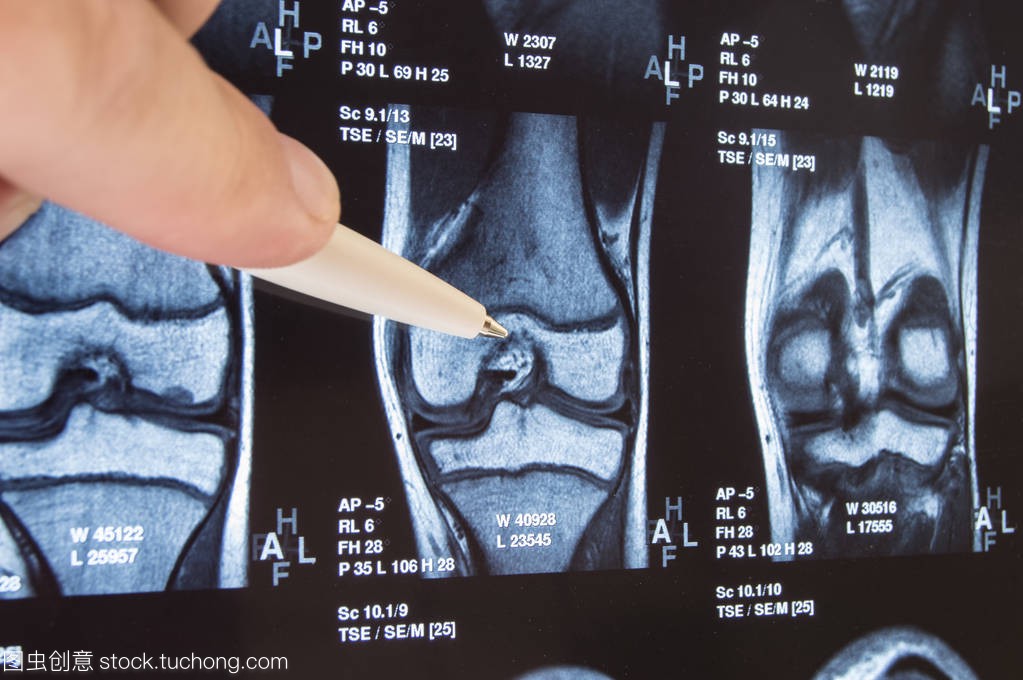

MRI技术系基于电磁波射频范围能量的吸收及释放。MRI成像的基础是被成像物体吸收及释放射频能量的时相与频率的三维变化。在医学成像中应用的系统已有许多,从0.3T、1.0T到3.0T不等。MRl优于其他成像方法之处在于其无电离辐射、软组织对比度较好、高通量成像及多平面成像。MRI检查需要时间较长乃是其一个缺点。MRI对发现 腱鞘炎、关节积液、滑膜增生、囊肿、中枢神经累及、软骨破坏及反应性骨变化均很有帮助。